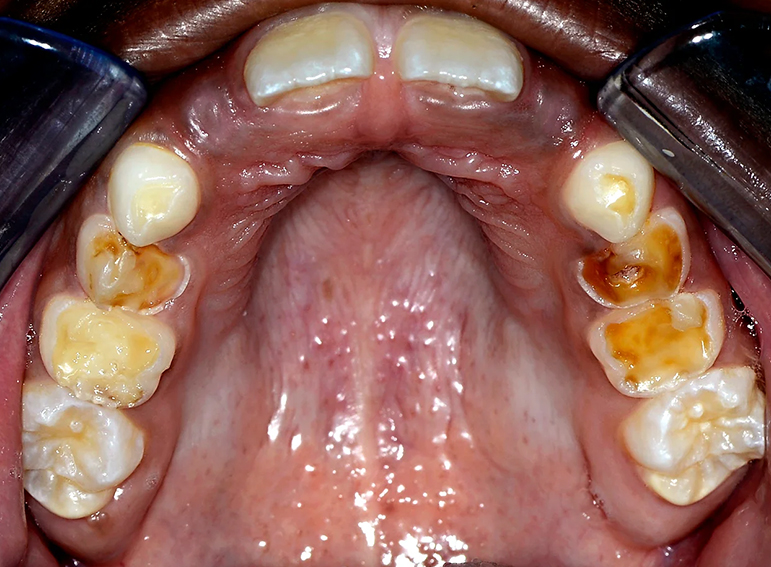

Hypoplastic primary molars: Placement of hall crowns, extraction of URD and ULD, composite restorations of LRD, LLD and C’s and fissure sealants of adult molars.